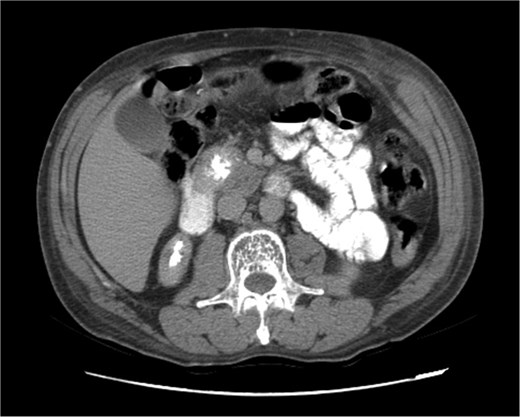

Upon admission in January 2025, the patient presented with altered mental status, dehydration, and hypoglycemia. The recurrence of hypoglycemic episodes was confirmed by laboratory studies and imaging, which identified a well-defined 3 cm mass in the pancreatic head on triphasic computed tomography (Figs 1–3). Given the diagnosis of recurrent malignant insulinoma and the possibility of resection, a surgical approach was chosen.

Triphasic computed tomography of the pancreas, arterial phase, showing a tumor in the head of the pancreas.